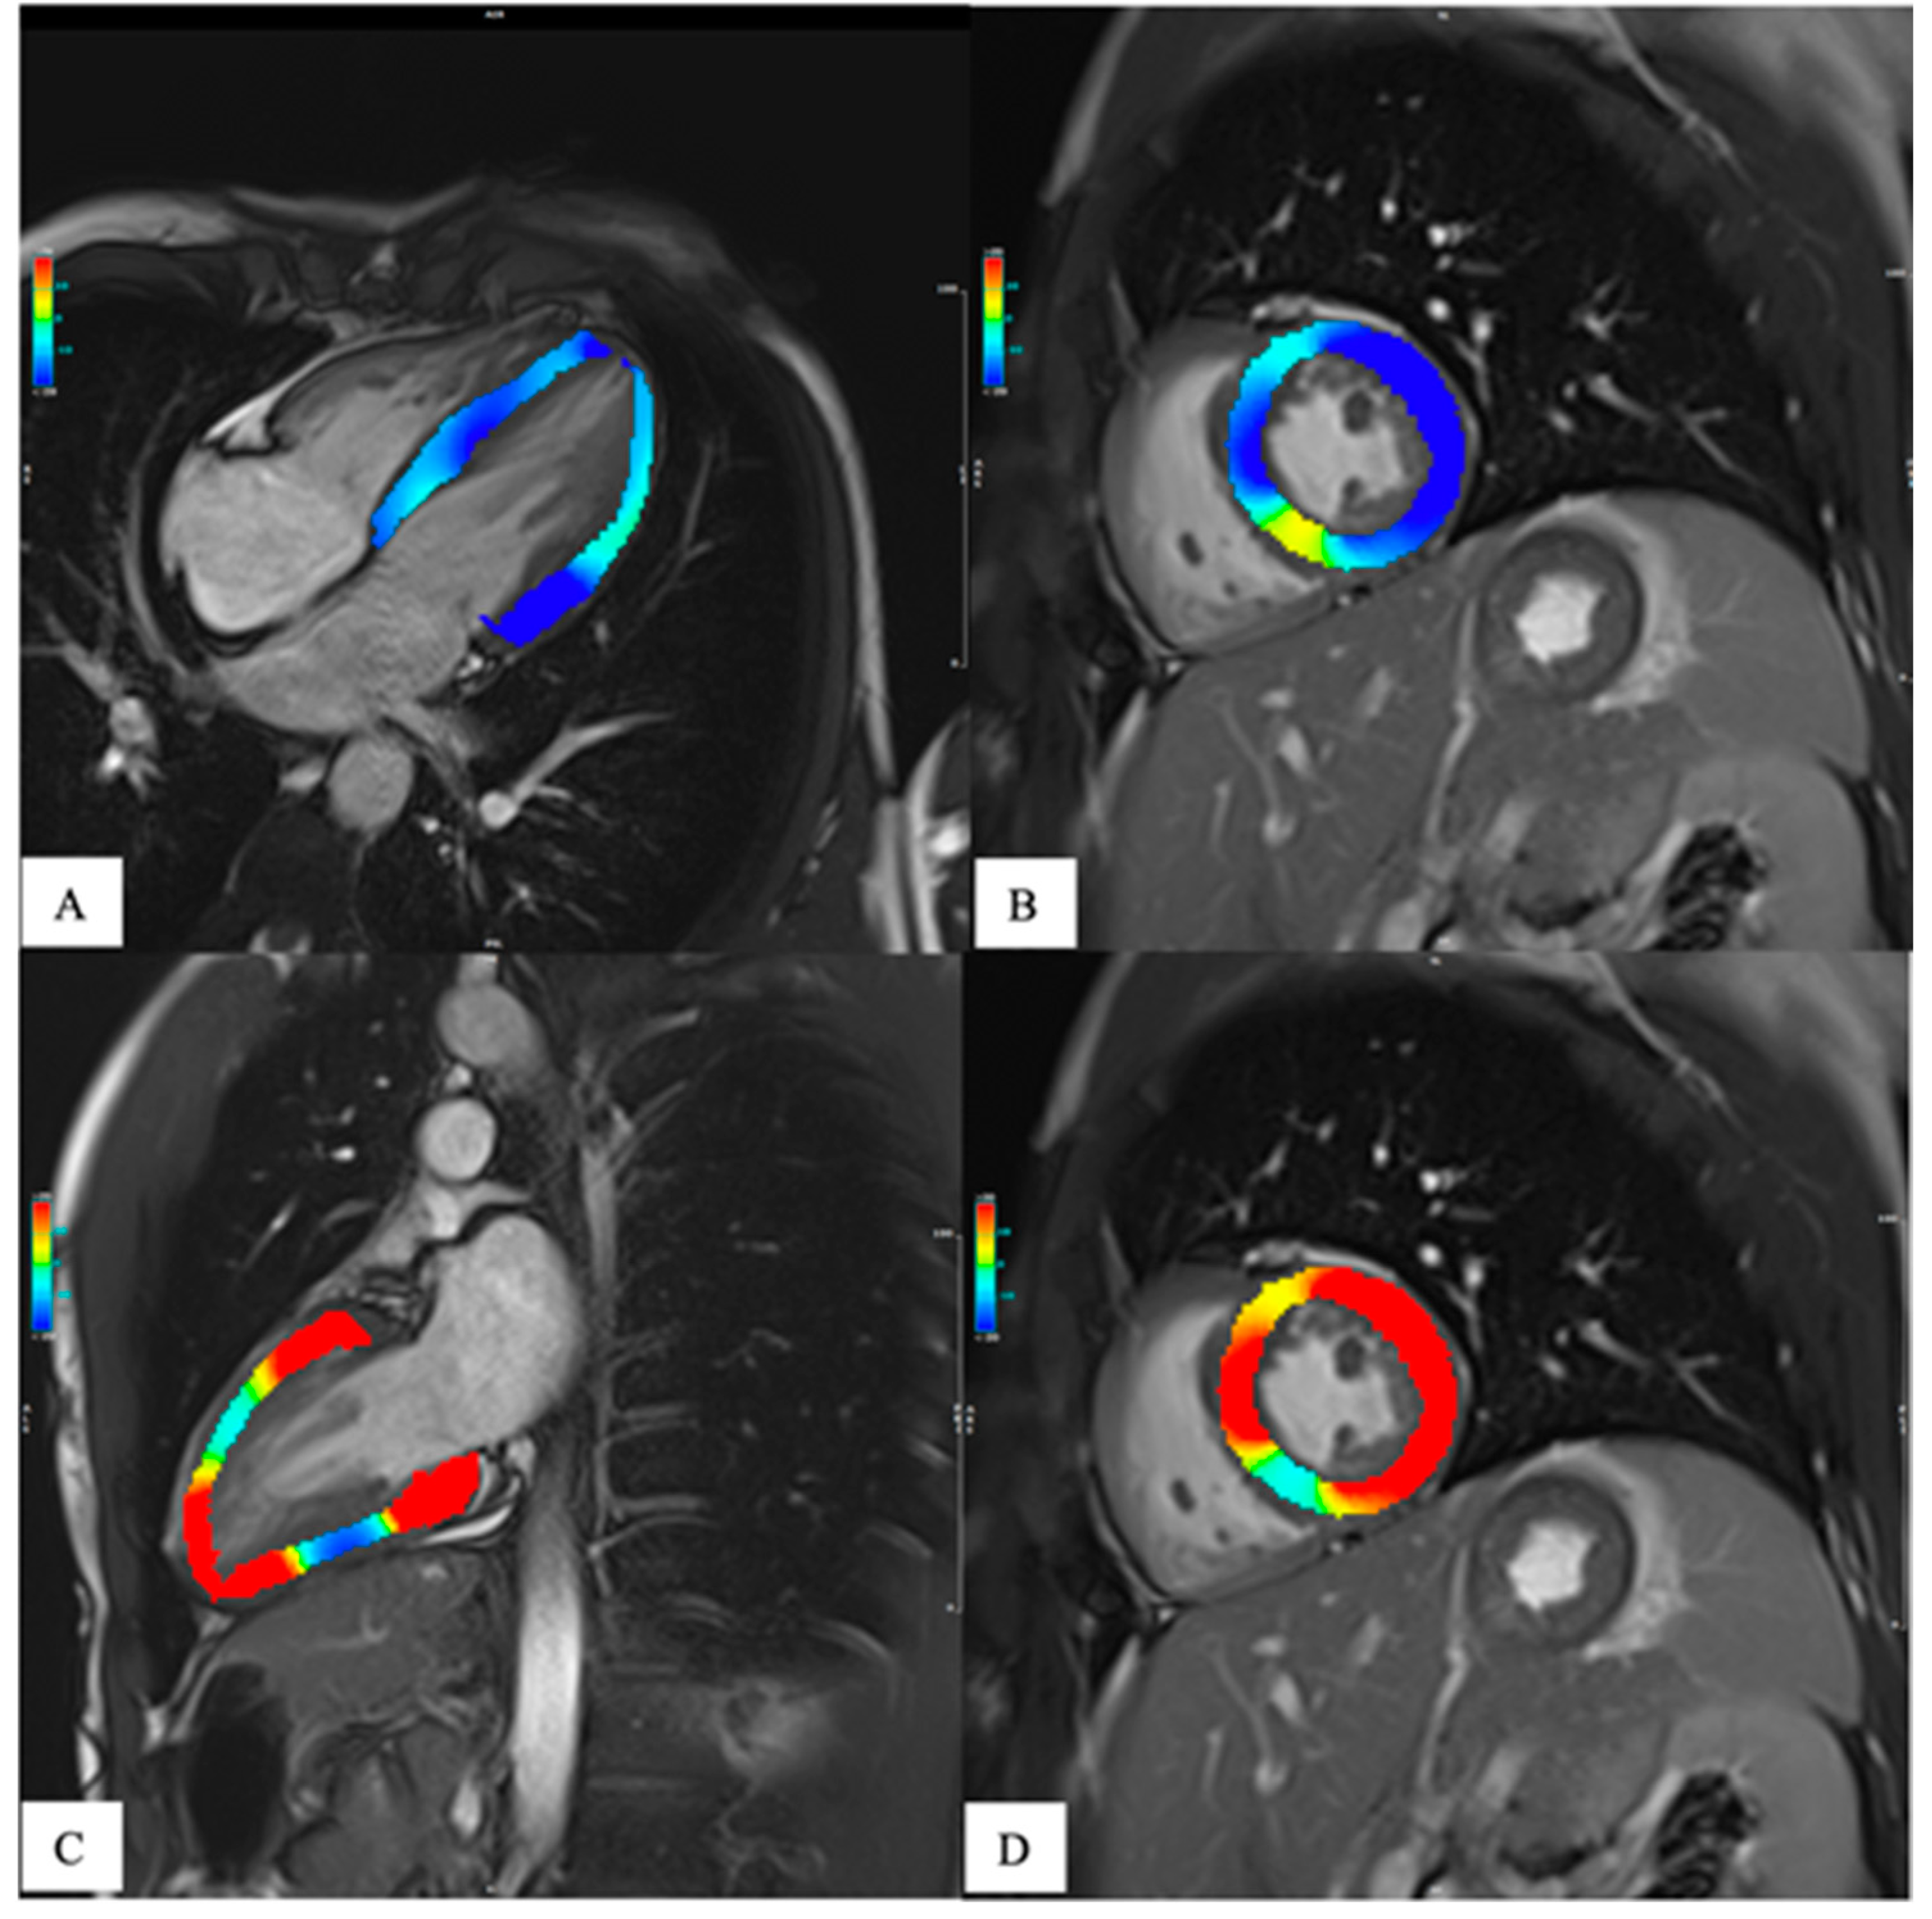

Initially, much of the research published about parametric imaging was focused on progress in acquisition methodology. This allowed to achieve numerous fast and robust mapping software, nowadays commercially available on the state-of-the-art CMR systems. And the evidence on the clinical value of CMR mapping from large clinical outcomes trials is rapidly growing. Thus, parametric mapping can be considered as a natural extension of comprehensive CMR protocols for a deep and quantitative myocardial assessment (Messroghli et al., 2017). Moreover, thanks to technological improvement, it is now possible to analyze the entire left ventricular myocardium with a global or segmental that showed the intrinsic advantage of higher sensitivity [Figure 3] (Meloni, Gargani, et al., 2023; Meloni, Pistoia, et al., 2023; Pepe et al., 2022).

The main limitation for spreading the mapping techniques in the routine clinical and research arena is due to its high reliance on the single scanner, on the type of sequence used and on imaging acquisition modality. This is the reason why normal reference values based on sex and age are recommended for each center considering that these parameters can be partially influenced by age and sex (Meloni et al., 2021, 2022; Messroghli et al., 2017) [Figure 4].

The need to a more in-depth characterization of heart function has led, in the last years, to the development of tissue tracking analysis. This technique provides a quantitative assessment of the global and regional kinetics of the myocardium, [Figure 3] giving adjunctive information about heart function other than those obtained by the grossly ejection fraction (EF) alone(J. Xu et al., 2022). In fact, the EF is a parameter of overall ventricular systolic function and does not provide information about regional myocardial kinetics and contractility nor allows evaluation of the diastole. Moreover, in many heart diseases, the EF is altered only late in the progression, leaving a diagnostic gap in asymptomatic or subclinical conditions. Since its introduction in the late 1980s, tissue tracking has been extensively developed and is now gaining popularity due to the development of software for fast and robust analysis and to research trends towards generating evidence of the adjunctive value of strain in early and differential diagnosis, risk stratification and prognosis determination of many heart diseases.(J. Xu et al., 2022) Recent evidence has given strength to this technique so that it is starting to be included in CMR assessment. As for mapping, the determination of normative values both for healthy subjects and disease specific population is important to avoid misdiagnosis.